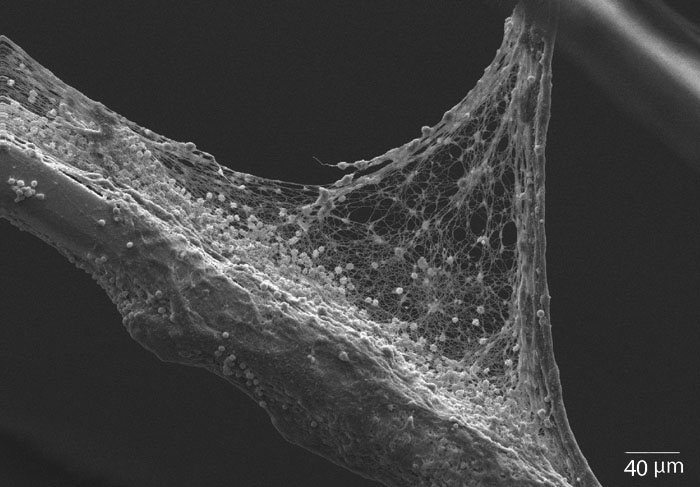

Aufnahme des Fibrinnetzwerks auf

Glasoberfläche mittels Atomic Force

Microscope (AFM).